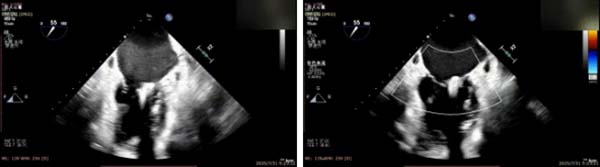

手术过程中,麻醉与围术期医学科副主任医师马金本确保麻醉过程平稳。心脏大血管外科主治医师董明亮穿刺股静脉置入血管鞘,并在心脏超声科梁皓主任及段福建教授TEE引导下,顺利穿刺房间隔,房间隔穿刺高度4.9cm。随后,在王安彪主任以及刘洋教授指导、心脏超声科梁皓主任TEE引导下,董明亮医师沿输送系统将延展呈“一字型”状态的国产夹合器送至左房,缓慢关闭夹合器并进行弹道测试。调整夹合器位置和方向后,董明亮医师再次将夹合器延展呈“一字型”完成跨瓣,避免发生腱索缠绕,成功捕获瓣叶后关闭夹合器,二尖瓣反流显著下降。夹合器完全解离后,超声示二尖瓣反流程度显著下降,残余反流0,平均跨瓣压差1mmHg,手术圆满成功。

房间隔穿刺

夹合器“一字型”状态进入左房

缓慢关闭夹合器

捕获瓣叶并放下Gripper

关闭夹合器